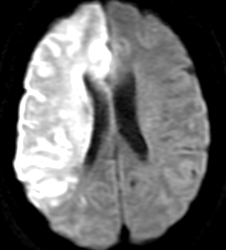

【心原性脳塞栓症】

最も重症なタイプが脳塞栓です。主に心臓の中で出来た血の塊(血栓)が血流に乗って運ばれ、脳の太い血管を詰めてしまうため急に重篤な片麻痺や意識障害、言語障害が出現するものです。心臓の中に血栓が出来る原因としては不整脈の一種の心房細動というものが重要です。アテローム血栓性脳梗塞と違い、いきなり血管がつまるため症状は突然に起こり、また太い脳血管がつまることが多いので症状も重い場合が多いと言えます。

Apoplexy 6

【MRI】

MRA

【MRA】

翌日のCT

【翌日のCT】

心房細動からの塞栓にて右内頸動脈が閉塞史、広範囲脳梗塞を呈している。翌日には脳が強く腫れてきている。